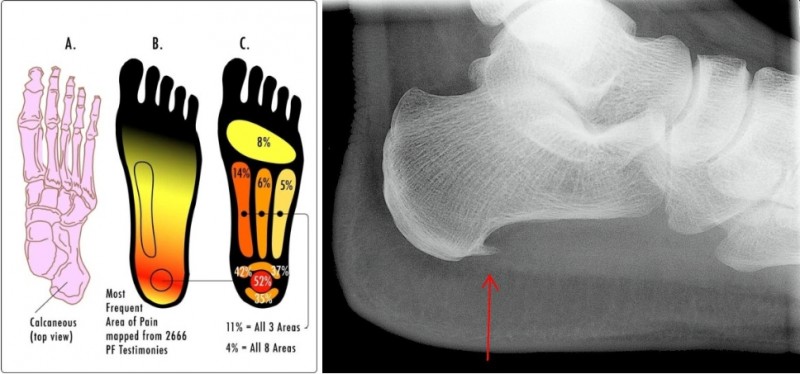

족저근막염은 발뒤꿈치뼈에서 시작해 발바닥 앞쪽으로 이어지는 강인한 섬유띠인 족저근막에 반복적인 미세 손상이 가해져 발생하는 염증성 질환입니다.

드물지만 발 뒤꿈치 뼈 부착부위에 뼈조각이 튀어나온 사람들 중 일부에서 발생하기도 합니다.

밤 사이 수축된 족저근막이 갑자기 늘어나면서 아침 첫발을 디딜 때 느껴지는 극심한 통증 발생

발뒤꿈치 안쪽에 집중되는 통증

발바닥 전체로 퍼지는 통증

특정 부위를 눌렀을 때 통증 발생